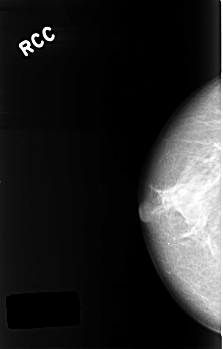

Digital Database for Screening Mammography

Volume: benign_06 Case: C-0326-1

C_0326_1.RIGHT_CC

RIGHT_CC LINES 4528 PIXELS_PER_LINE 2888 BITS_PER_PIXEL 12 RESOLUTION 50 NON_OVERLAY

FILE: C_0326_1.LEFT_CC.OVERLAY

TOTAL_ABNORMALITIES 1

ABNORMALITY 1

LESION_TYPE MASS SHAPE OVAL MARGINS ILL_DEFINED

ASSESSMENT 3

SUBTLETY 3

PATHOLOGY BENIGN